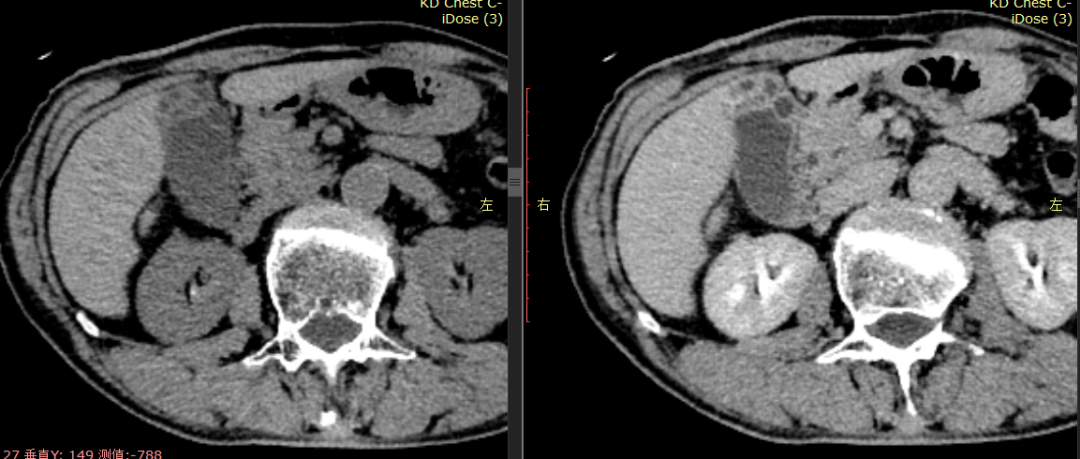

CASE 4